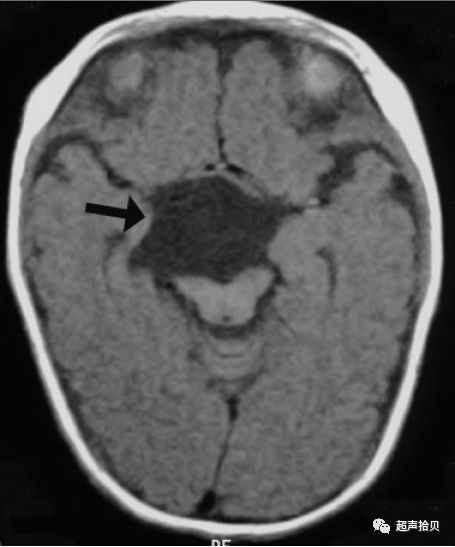

图4:妊娠26周时的产前MRI:第三脑室蛛网膜囊肿的横向(A),矢状(B)和冠状面(C)平面引起脑室扩张

图5:出生后1周进行T1加权轴位MRI扫描。 侧脑室的后角和前角,特别是第三脑室,被蛛网膜囊肿占据。